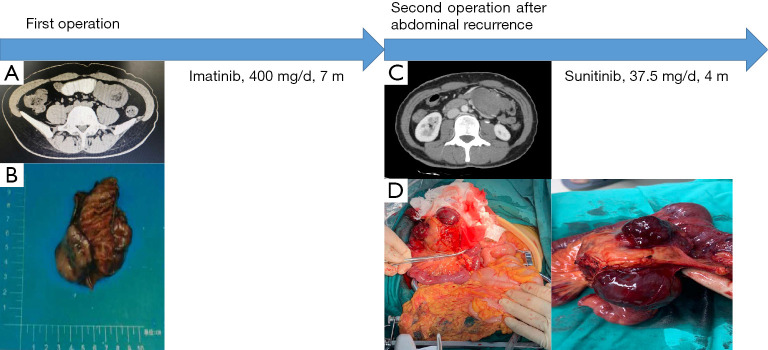

佳学基因肿瘤耐药与复发病案集中收录了一例 42 岁女性,23 年前行阑尾切除术,18 年前行剖宫产,无特殊个人史、婚姻史或家族史。 2020 年 4 月,患者入住当地医院,主诉间歇性腹部绞痛 >1 个月,过去 2 天加重。 腹部计算机断层扫描 (CT) 显示左侧中腹部中线小肠有小肠型肠套叠(见图 1A)。

术中发现小肠近端和中段有一肿瘤,大小约4cm×3cm×2cm,质地坚韧(见图1B)。 未见其他异常体征,如腹水或腹膜内转移。 接下来,对小肠和周围小肠的肿瘤进行了切除。

患者术后恢复顺利,入住佳学基因合作医院进行肿瘤基因检测。 结果确定了 PDGFRA 12 外显子 c.1741C>T (p.P581S) 突变。 根据中国临床肿瘤学会(CSCO)指南,患者的GIST属于高危级别,复发、转移和肿瘤相关死亡风险高。 因此,在 2020 年 5 月,肿瘤靶向用药剂师开始用口服伊马替尼(400 毫克/天)治疗患者。 患者在药物治疗期间未出现药物不良反应,2020年7月患者腹部CT检查结果未见异常。

2020年11月,患者出现左下腹隐痛症状。 2020年11月腹部CT示盆腔内有少量积液,左上腹腔脐部有一团软组织影(大小约43mm×43mm×39mm), 它与在小肠手术中观察到的上述吻合相邻(参见图 1C)。 考虑GIST复发的可能,不排除GIST转移。 行正电子发射断层扫描/CT检查,结果显示GIST术后,吻合口无明确复发征象,左腹部邻近有一个代谢亢进的软组织肿块。 因此,考虑淋巴结转移的可能性。 患者就诊于佳学基因合作医院,诊断如下:(一)GIST术后复发; (二)术后阑尾炎; (III) 术后剖宫产。

查体结果如下:左上腹触胀; 没有其他积极迹象。 2020年12月,患者在全身麻醉下接受了剖腹探查术。 术中在原空肠-空肠吻合口下方小肠系膜发现一大小约8cm×7cm×6cm的肿瘤(见图1D)。 切除了小肠系膜肿瘤和部分小肠。 患者术后恢复顺利。